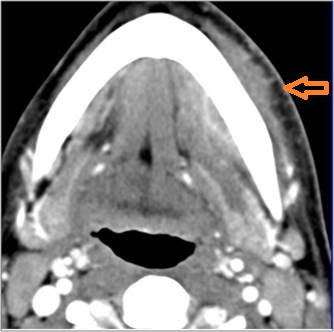

There is excessive enhancement or thickening of the fat or other soft tissues within or surrounding the buccal space, masticator space, floor of the mouth, submandibular space or the adjacent superficial fascia or subcutaneous fat and skin. [Yes/No]

There is subperiosteal abscess or an abscess cavity adjacent to or involving the maxilla or mandible. [Yes/No]

There is endodontal or periodontal disease that might be causing cellulitis or abscess. [Yes/No]